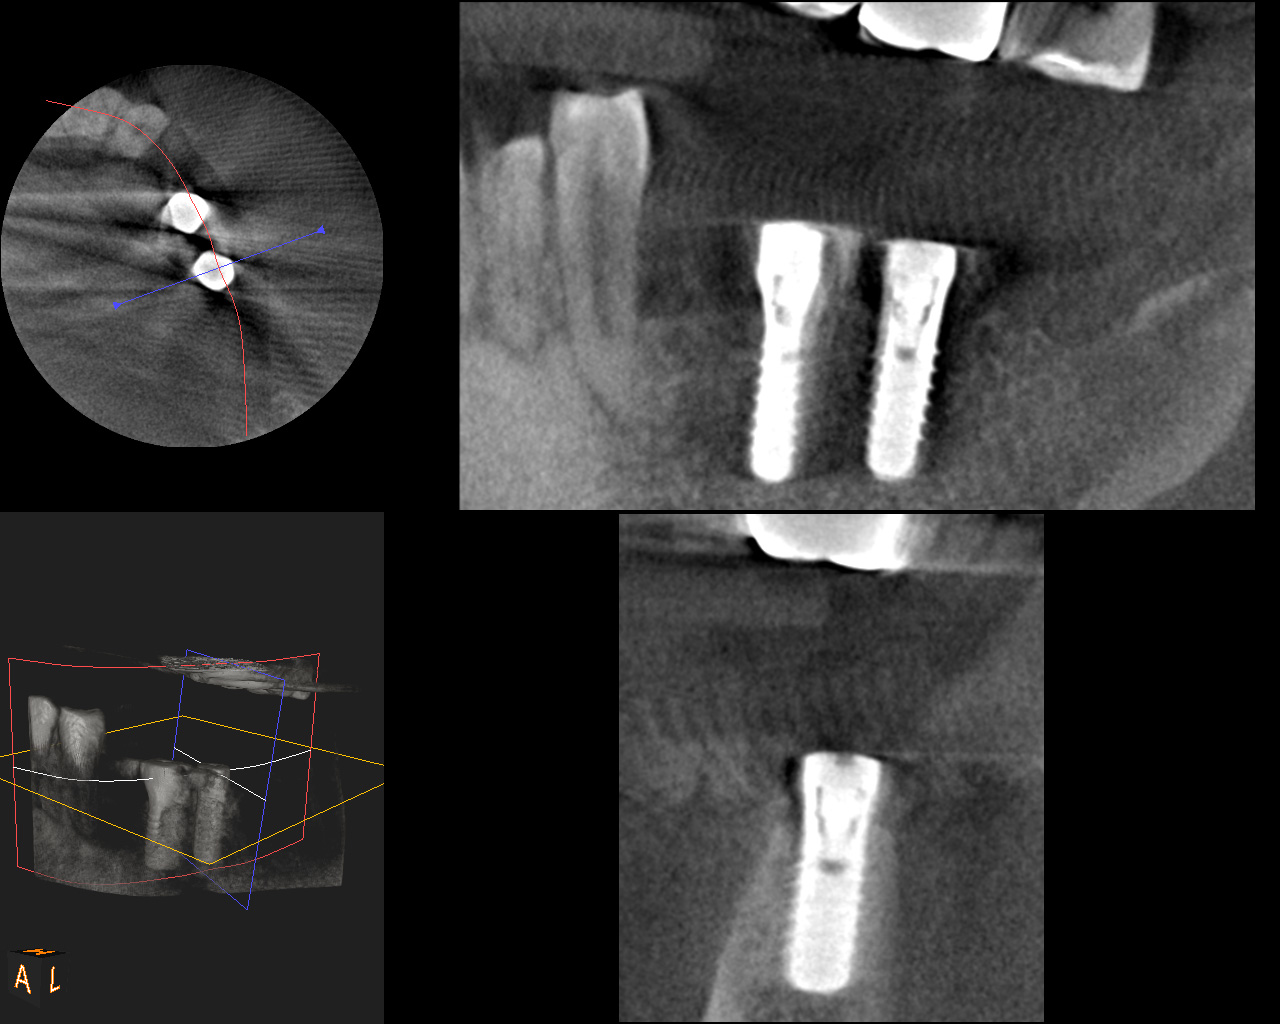

複数の歯に及び歯が失われているためCT画像上で診断と設計を行い、理想的な位置に歯を作ることができるように、サージカルガイドと言われるインプラント手術補助用マウスピースを用いてインプラント手術を行った。

術前CT

術後CT